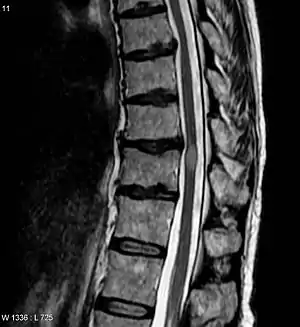

| Acute myelitis | intramedullary lesion > 3 contiguous segments, or spinal atrophy ≥ 3 contiguous segments |

In NMOSD, areas of brain tissue that appear normal in conventional magnetic resonance imaging (MRI) can show damage in diffusion tensor imaging (DTI), although less so compared to multiple sclerosis (MS).[19]

Most research into the pathology of NMO has focused on the spinal cord. The damage can range from inflammatory demyelination to necrotic damage of the white and grey matters. The inflammatory lesions in NMO have been classified as type II lesions (complement-mediated demyelination), but they differ from MS pattern II lesions in their prominent perivascular distribution. Therefore, the pattern of inflammation is often quite distinct from that seen in MS.[12][20]